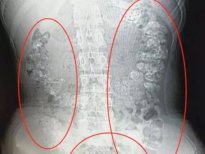

Kabızlık şikayetiyle Doğu Çin'in Zhejiang Eyaletindeki Zhuji Halk Hastanesi'ne kaldırılan Xiao Shen'in midesinden 100 'Tapioca' denilen jelibon toplarının yapıştığı saptandı. Jelibon toplarının mideye yapışma sebebi ise doktorları bile şoke etti.

Çin'de 14 yaşındaki Xiao Shen, 4 gün boyunca kabızlık çekince hastaneye kaldırıldı. Midesinden öyle bir şey çıktı ki doktorlar bile şoke oldu.